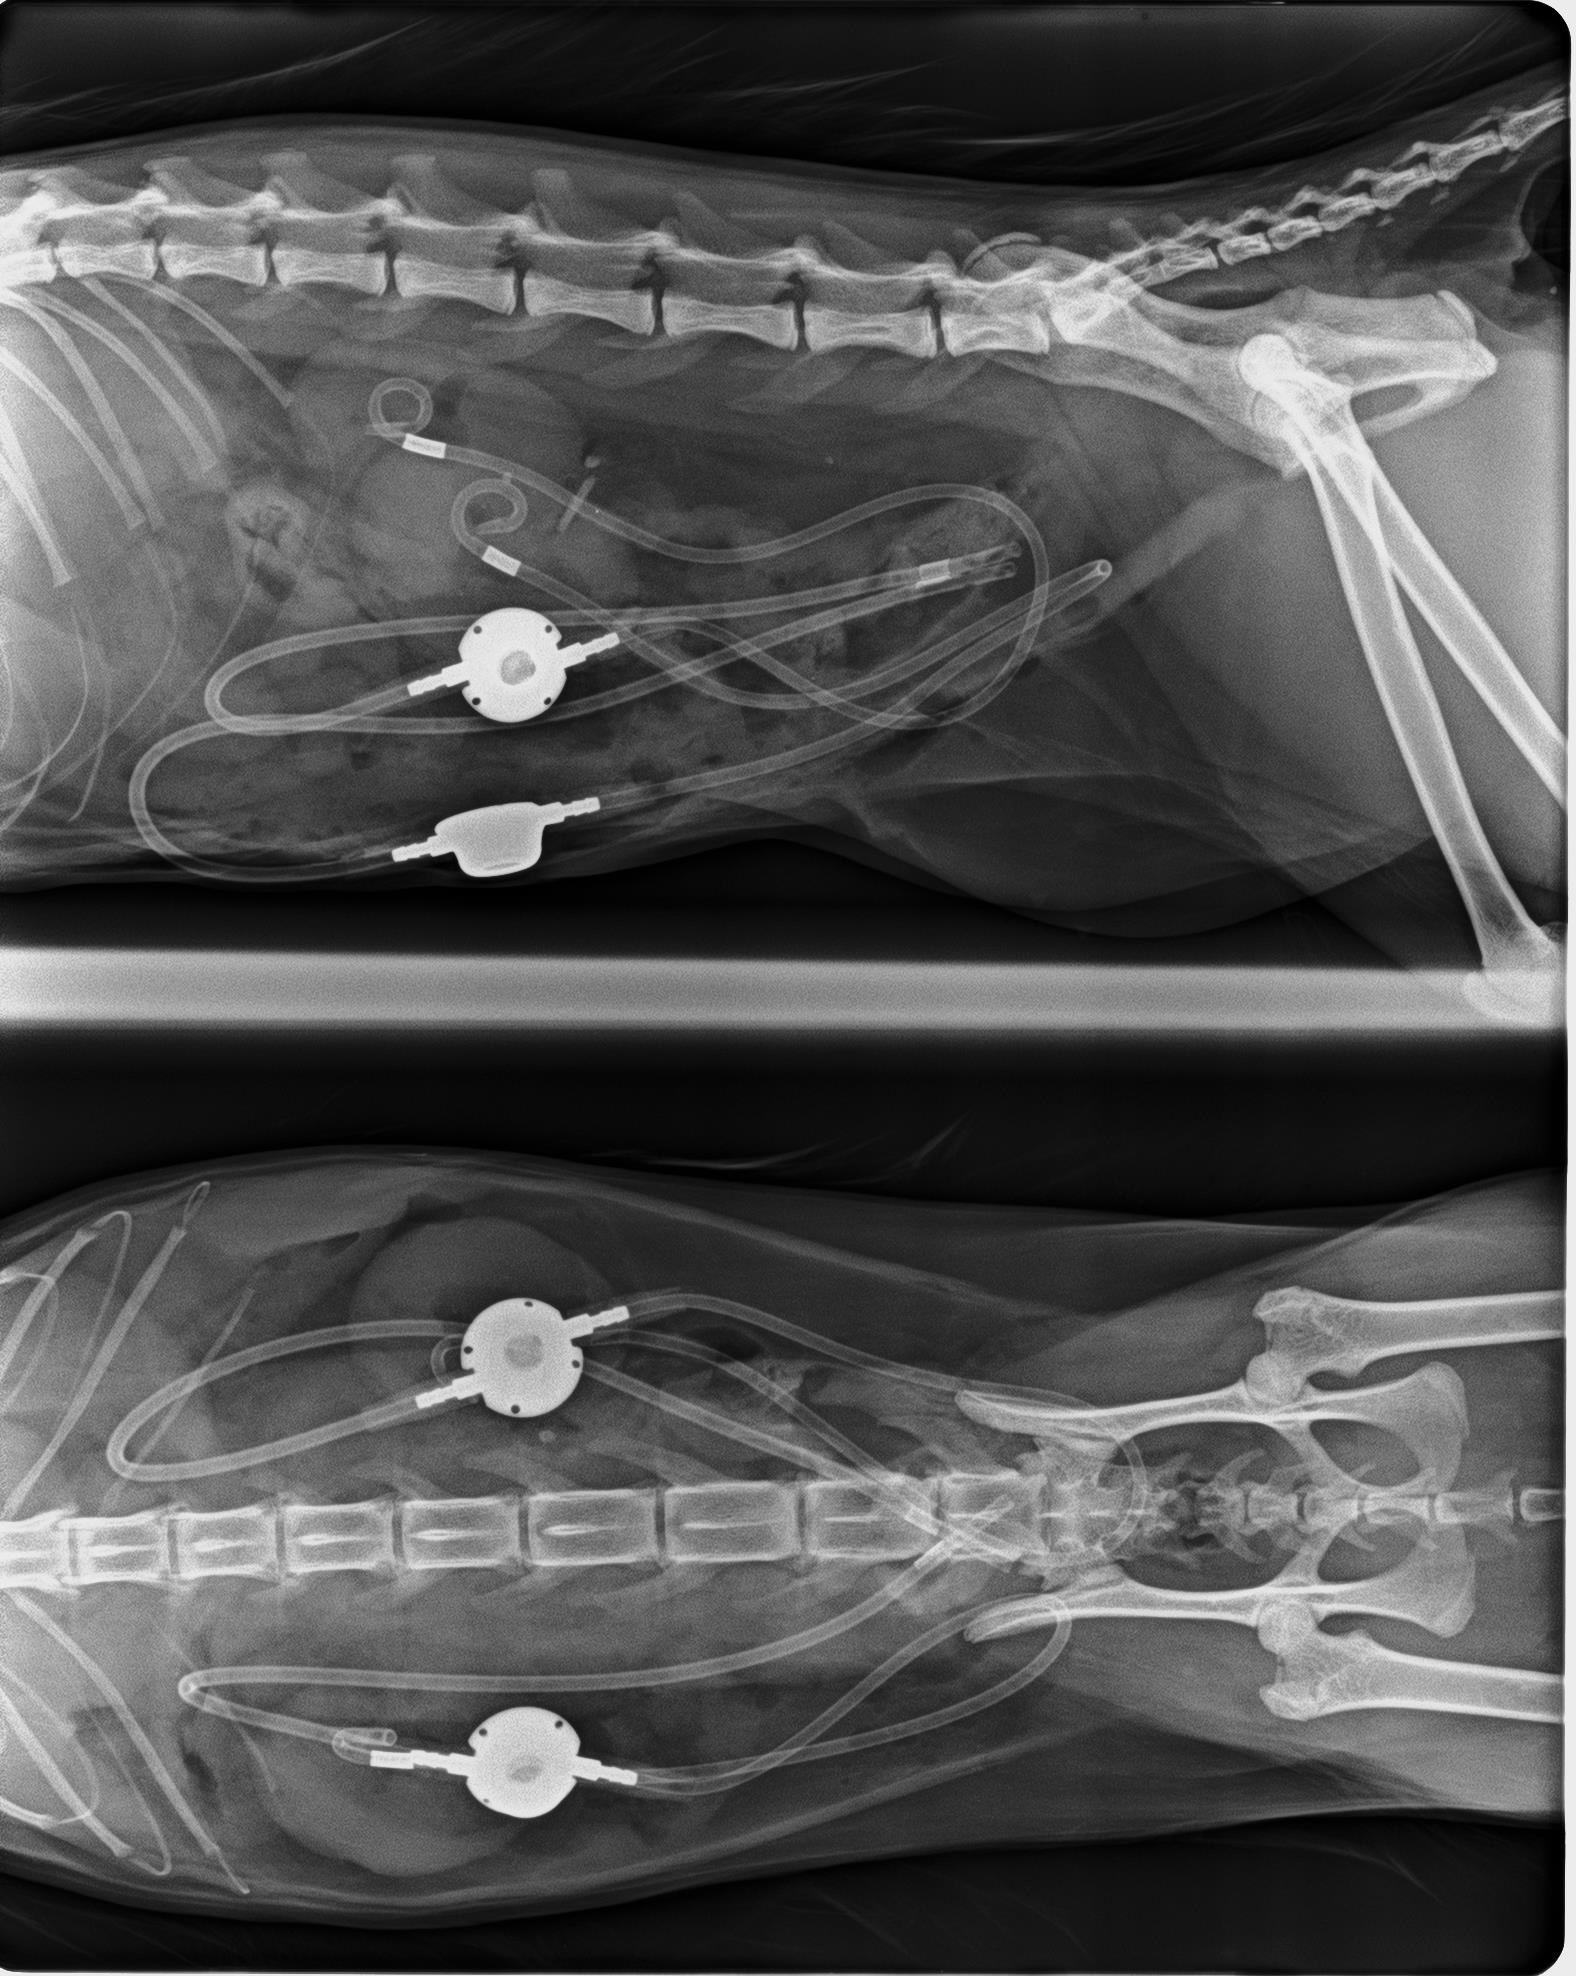

Implantación de dos catéteres de bypass ureteral SUB en gato

En este caso, les presentamos a Lili, una gata de tan solo 2 años de edad que presentaba una obstrucción bilateral.

En las radiografías se puede comprobar la presencia de litiasis en el interior del riñón izquierdo y dos pequeños cálculos en los uréteres.

En este caso al tratarse de una gata joven que además presentaba cálculos en la pelvis renal decidimos implantar dos catéteres de bypass ureteral SUB.

La presencia de cálculos en los riñones pueden dar lugar a futuras obstrucciones ureterales y siendo un paciente tan joven y además con patología bilateral se descartó la opción de ureterotomía por los posibles riesgos postoperatorios a corto y largo plazo.